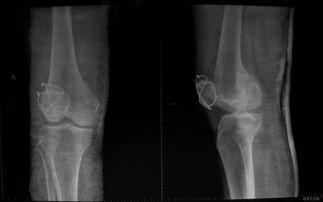

首先,咱们得弄明白什么是髌骨骨折。髌骨,也就是我们常说的膝盖骨,是人体最大的籽骨,位于膝盖前方。它连接股骨和胫骨,起到稳定膝关节的作用。髌骨骨折,就是膝盖骨断裂了,这种情况可能是因为跌倒、撞击或者剧烈运动造成的。